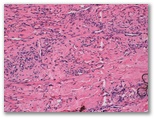

R3-1514-Mujer de 35 años, sin antecedentes patologicos relevantes que consulta por adenopatías hiliares y las lesiones cutáneas que observas en la imagen y en la biopsia.

a)descripción, dx, formas clínico-patologicas

Diagnostico